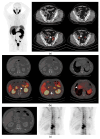

This prospective study aimed to (1) compare the diagnostic performance of 68Ga-PSMA-11 PET/CT with respect to conventional imaging (computed tomography (CT) and bone scintigraphy (BS)) in the primary staging of high-risk prostate cancer (PCa) patients and (2) validate PSMA-PET/CT accuracy in pelvic nodal staging in comparison with postoperative histopathology and assess PSMA-PET/CT's impact on patient management. Sixty castration-sensitive high-risk (ISUP 4-5 and/or PSA > 20 ng/mL and/or cT3) PCa patients eligible for radical prostatectomy were enrolled (median PSA 10.10 [IQR: 6.22-17.95] ng/mL). PSMA-PET/CT, compared with CT, identified nodal (N) and/or distant metastases (M1) in 56.7% (34/60) vs. 13.3% (8/60) (p < 0.001) of patients: N + 45% vs. 13.3% (p < 0.001), M1a 11.7% vs. 1.7% (p = 0.03), M1b 23.3% vs. 1.7% (p < 0.001). Compared with BS, PSMA-PET/CT localized unknown skeletal metastases in 15% (9/60) of cases, with no false negative findings. Overall, PSMA-PET/CT led to a TNM upstaging in 45.0% (27/60) of cases, with no evidence of downstaging, resulting in a change in management in up to 28.8% (17/59) of patients. Compared with histopathology data (n = 32 patients), the per-patient accuracy of PSMA-PET/TC for detecting pelvic nodal metastases was 90.6%. Overall, the above evidence supports the use of PSMA-PET/CT in the diagnostic workup of high-risk prostate cancer staging.